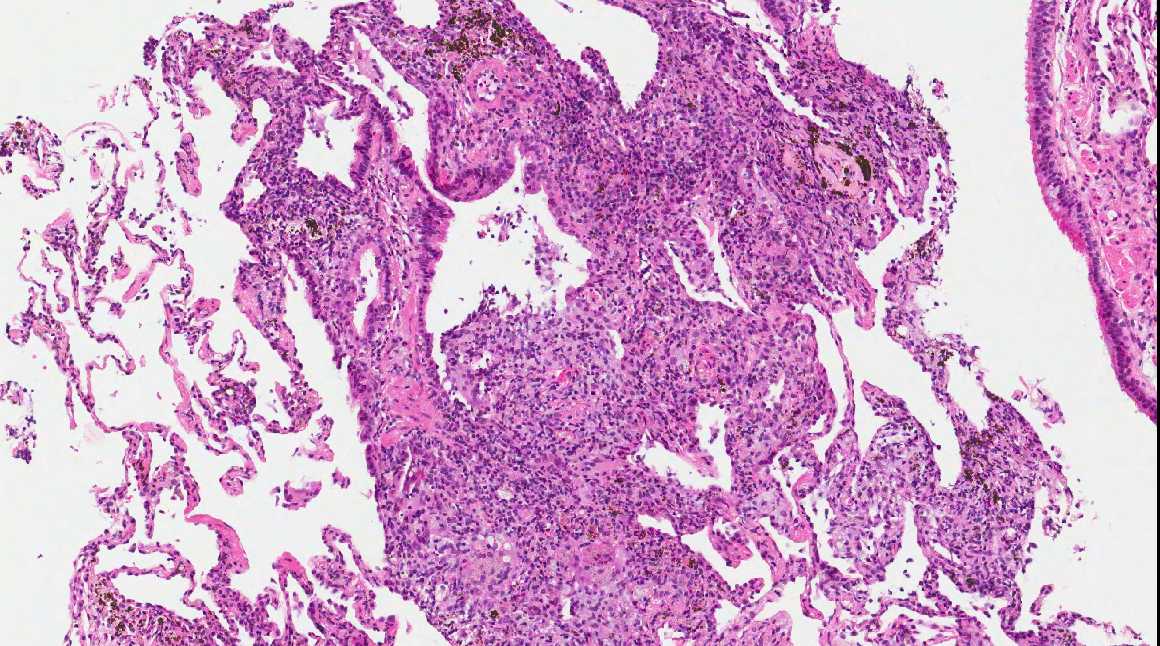

A 71 year old man with recent history of meningitis presented with recurrent episodes of pneumonia. High resolution CT scans showed crazy paving and tree in bud images. The patient underwent a transbronchial biopsy.

Micro images:

Diagnosis: Aspiration with granulomatous bronchiolitis and lipoid pneumonia

Aspiration of particulate matter, traditionally observed at autopsy, has also been described in debilitated patients, who often have a history of recurrent pneumonia, which is often unrecognized (Am J Surg Pathol 2007;31:752, Am J Surg Pathol 2010;34:1456). It usually (88%) shows bronchiolitis obliterans organizing pneumonia, often with multinucleated giant cells, acute bronchopneumonia / bronchiolitis or suppurative granulomas. Foreign material is usually but not always present (Am J Surg Pathol 2011;35:426).

The differential diagnosis of pulmonary granulomatous inflammation is broad and requires special stains, culture and clinical correlation (Ann Diagn Pathol 2003;7:127, Histopathology 2007;50:289).

Lipoid pneumonia is often an incidental postmortem finding associated with debilitating disease. The lipid may be exogenous (from nasal sprays or inhalation of other lipid containing substances) or endogenous (bronchial obstruction).

A 71 year old man with recent history of meningitis presented with recurrent episodes of pneumonia. High resolution CT scans showed crazy paving and tree in bud images. The patient underwent a transbronchial biopsy.

Micro images:

Diagnosis: Aspiration with granulomatous bronchiolitis and lipoid pneumonia

Aspiration of particulate matter, traditionally observed at autopsy, has also been described in debilitated patients, who often have a history of recurrent pneumonia, which is often unrecognized (Am J Surg Pathol 2007;31:752, Am J Surg Pathol 2010;34:1456). It usually (88%) shows bronchiolitis obliterans organizing pneumonia, often with multinucleated giant cells, acute bronchopneumonia / bronchiolitis or suppurative granulomas. Foreign material is usually but not always present (Am J Surg Pathol 2011;35:426).

The differential diagnosis of pulmonary granulomatous inflammation is broad and requires special stains, culture and clinical correlation (Ann Diagn Pathol 2003;7:127, Histopathology 2007;50:289).

Lipoid pneumonia is often an incidental postmortem finding associated with debilitating disease. The lipid may be exogenous (from nasal sprays or inhalation of other lipid containing substances) or endogenous (bronchial obstruction).